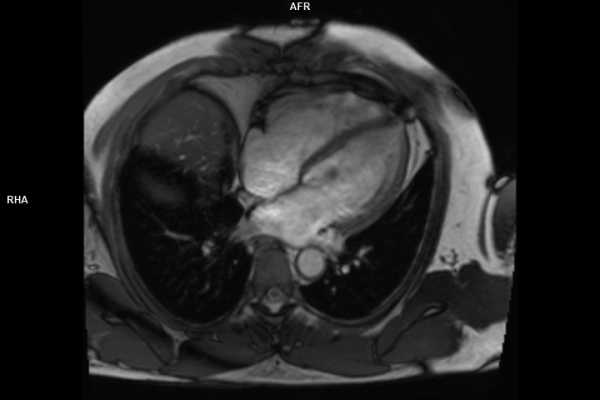

• Kardiovaskuläre Bildgebung (MRT- und CT-Untersuchungen des Herzen)

Im Zentrum all meiner Bemühungen steht stets der Mensch. Mich motiviert am Beruf besonders die detektivische Spurensuche durch einen nicht-invasiven Blick in den menschlichen Körper. Radiologische Einschätzungen sind entscheidend für eine korrekte Diagnose und die Wahl der Therapie durch die behandelnden Ärzte.

Wir bieten ein breites Spektrum an Untersuchungen an, von Standarduntersuchungen der Gelenke, Organe oder großflächigen Körperregionen bis zu Spezialuntersuchungen zum Beispiel des Herzen oder der Gefäße. Zusätzlich werden Angiographien (Darstellung von Blutgefäßen), Endometriose-Abklärungen und Mamma-Untersuchungen durchgeführt. Genauere Details können Sie der MRT/CT-Übersicht und der Preisliste entnehmen, oder Sie wenden sich direkt an unser Team, das Sie gerne zur passenden Untersuchung berät.

Die MRT (Magnetresonanztomographie) arbeitet mit Magnetfeldern und Radiowellen und eignet sich besonders für Untersuchungen der Weichteile wie Gehirn, Muskeln oder Gelenke. Die CT (Computertomographie) nutzt Röntgenstrahlen und liefert schnelle, hochauflösende Bilder, insbesondere für Knochen, Lunge oder innere Organe. Die Wahl der jeweiligen Untersuchung richtet sich an das individuelle Krankheitsbild und wird bei der Überweisung festgelegt.